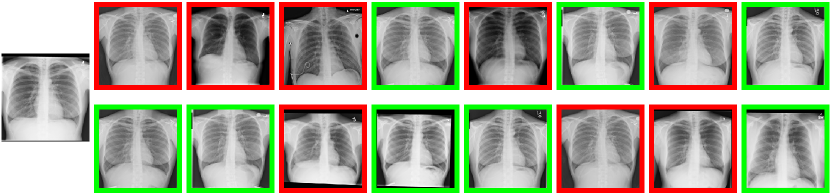

Figure 5: Qualitative results of MIR. In the top, middle and bottom sub-figures, we show the qualitative retrieval results of Derment, Retina and X-ray datasets, respectively. The query image is shown on the left of each sub-figure. On the right of each sub-figure, there are two rows. The first row shows the top-8 retrieval results by the specialist MIR model and the second row shows the top-8 retrieval results by the multi-source MIR model. The correct retrieval images are marked by green and the incorrect images are marked by red.

In Fig. 3, we show the Recall@1 of the multi-source MIR model. We can find that the early over-fitting problem no longer happens because of training by distillation. Given pairs of images, the distribution of the ratios of the distances measured by the multi-source MIR model and the specialist MIR models is shown in Fig. 4. For all the three sources, we can find that the mean values of the ratio are greater than 1, meaning that the distances become larger when measured by the multi-source MIR model. For Dermnet and Retina sources, the variances of the inter-class distance ratios are smaller than the intra-class distance ratios. Some of the qualitative image retrieval results are shown in Fig. 5. In the top, middle and bottom sub-figures of Fig. 5, we show the retrieval results of Derment, Retina and X-ray datasets, respectively. On the right of each sub-figure, the first row shows the top-8 retrieval results by the specialist MIR model and the second row shows the top-8 retrieval results by the multi-source MIR model. The correct retrieval images are marked by green boxes and the incorrect images are marked by red boxes.